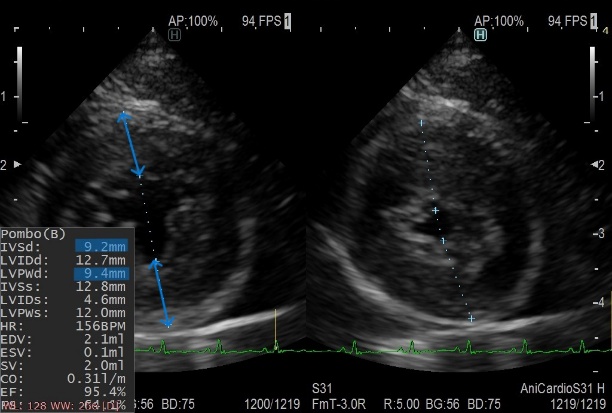

肥大型心筋症は、左心室の筋肉が過剰に分厚くなってしまい、心臓がうまく動けなくなってしまう病気です。原因のほとんどは遺伝であり、アメリカン・ショートヘアやメイン・クーンで多いといわれていますが、すべての猫で発症する可能性があります。発症の年齢も若齢から高齢まで様々です。

心筋が肥大して左心室の内径が極端に狭くなることで、左心房に血液が渋滞し、血栓を形成することがあります。この血栓が、後ろ足の付け根の動脈に詰まることがありますが、多くは何の前触れもなく発症します(動脈血栓塞栓症)。突然、後ろ足に麻痺を伴う激痛が走り、そのまま突然死となってしまうこともあります。